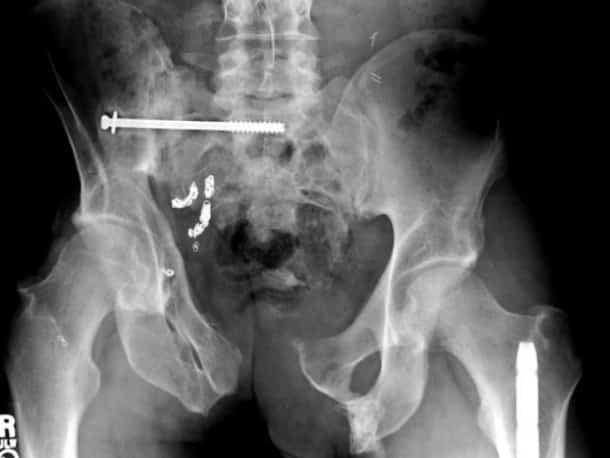

Accident, incident de pistolet à clous ou introductions douteuses de choses douteuses dans des parties douteuses de leur corps…voilà un petit aperçu de ce que voient les médecins au quotidien…

Certaines radiographies sont impressionnantes mais relèvent d’accidents…d’autres en revanche…